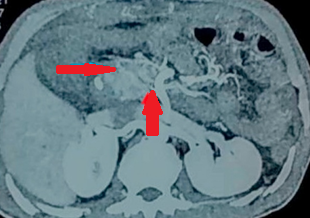

CT Angiography. Presence of a ruptured pseudoaneurysm of the common hepatic artery (Courtesy Dr. V. Penopoulos)